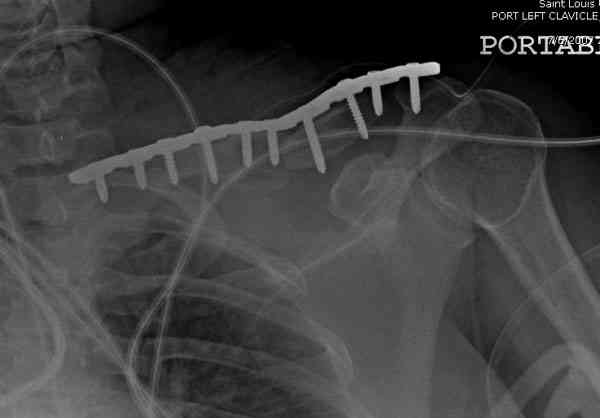

Недавно разбирали случай ложного сустава.

45 летная женщина после автоаварии, алкоголь 163 и 20 летним стажем курения.

Консервативное лечение, через 8 мес. операция Rockwood pin с костной пластикой в нашем городе другим врачом. После 8 недели падение, гвоздь удален оперирующим хирургом, больная направлена к нам. Фиксация реконструктивной пластиной с трикортикальным графтом, добавлен BMP-2. Для стабилизации фиксацию провели через акромион.

Вот уже два месяца больная также продолжает жаловаться на боли, буквально на днях удалили акромиальную часть пластины с специальной пилой с алмазным покрытием для медицинского металла. До сих пор судьба ложного сустава неизвестна....

|

Второй случай тоже недавно оперирован по поводу

ложного сустава, в марте травма, через 4.5 половиной

операция..